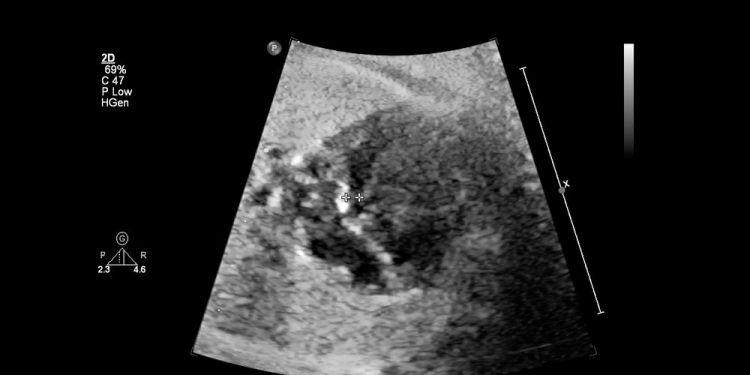

Bronchogenic cysts are usually found on a routine prenatal ultrasound, but they can also be seen on chest X-rays of newborns. They look like white, lumpy masses that are sometimes surrounded by tiny dark circles and are a common sign of a possible obstructed airway.